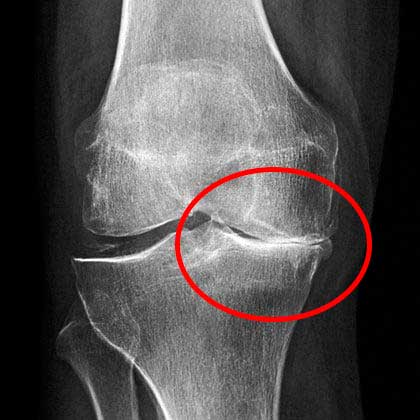

Beginilah kondisi kerusakan sendi lutut saat dilihat melalui rontgen